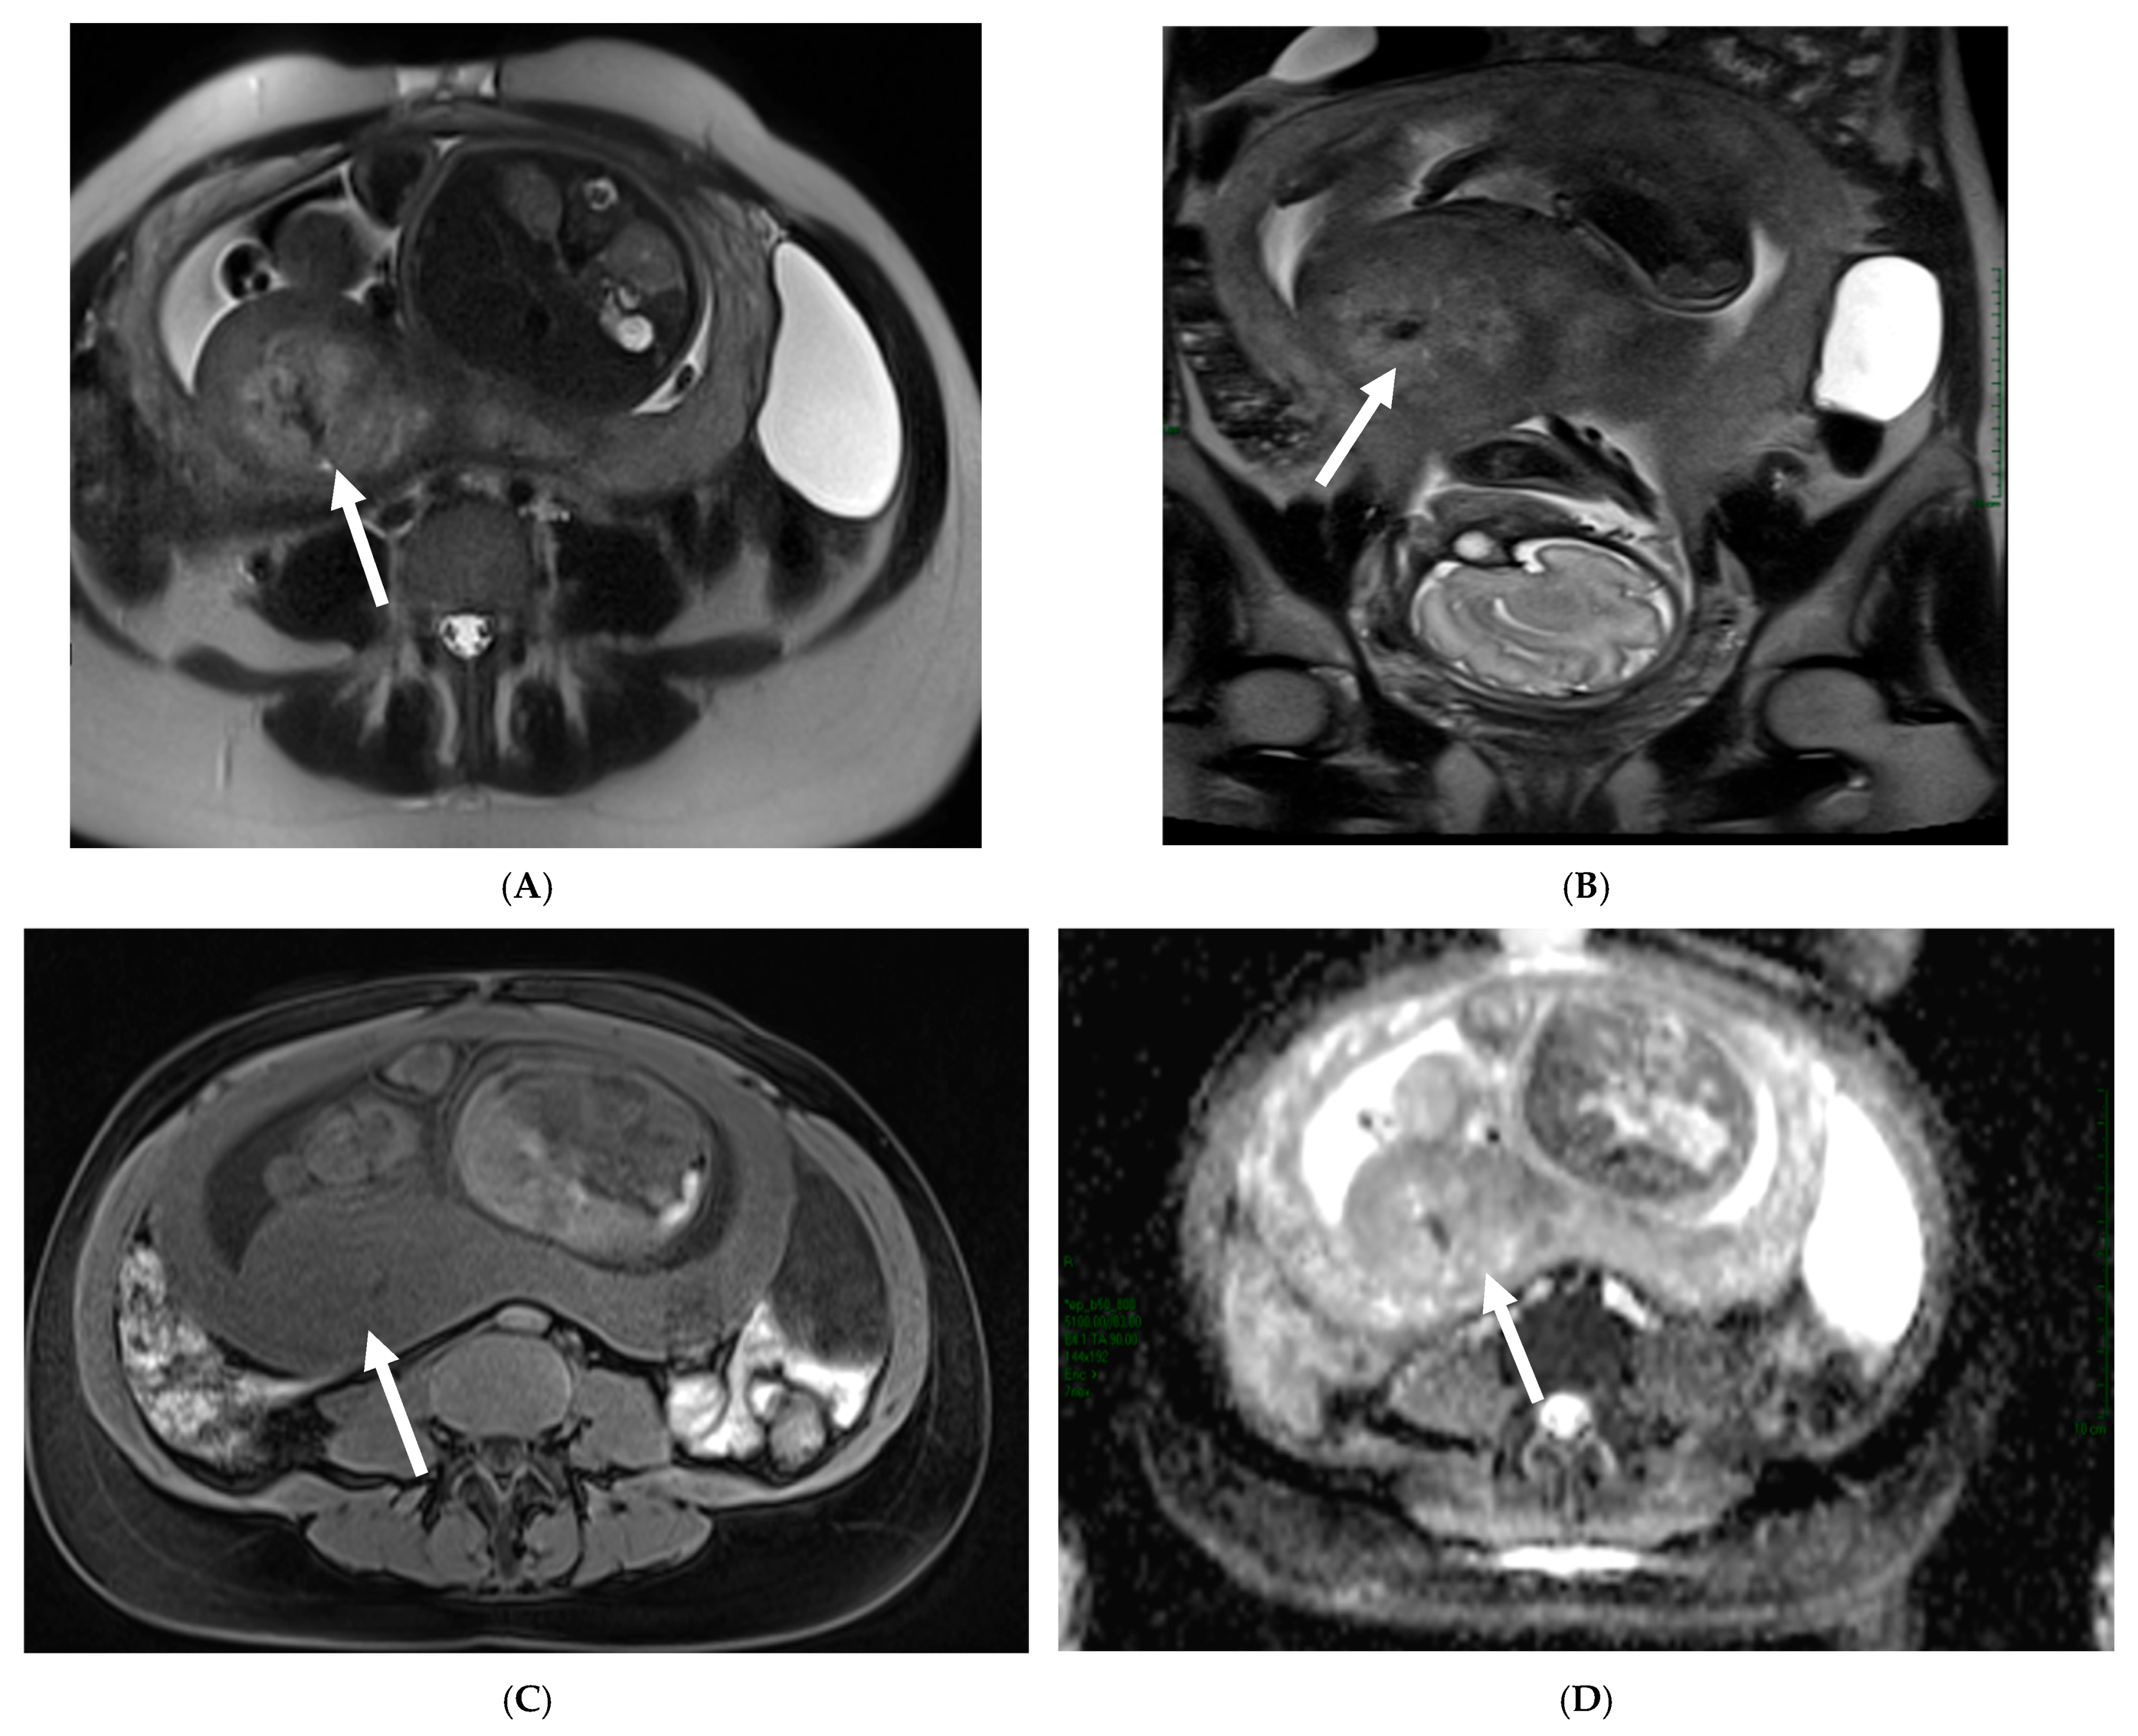

3.2.2. Imaging

3.2.3. Mimickers of Malignancy

3.4.2. Imaging